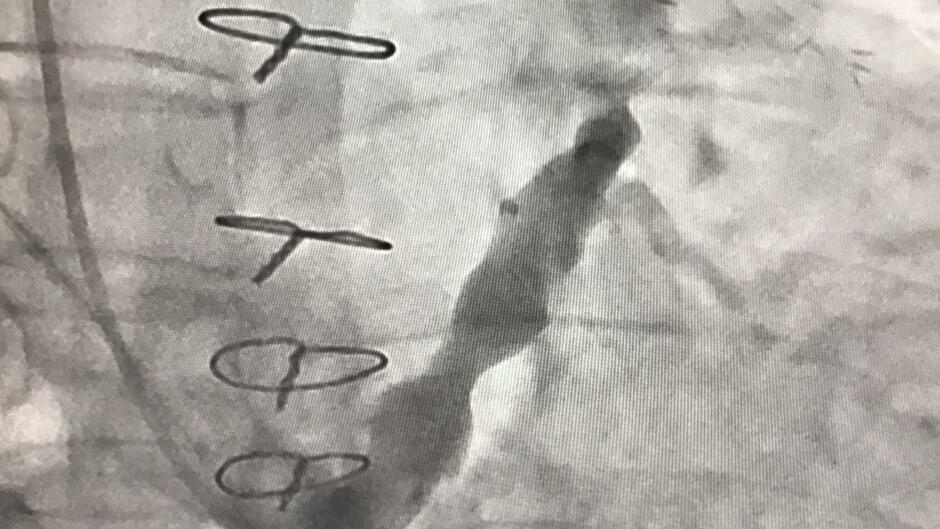

Specjaliści z I Kliniki Kardiologii Uniwersyteckiego Centrum Klinicznego w Gdańsku jako drugi zespół na świecie zastosowali implant A-Flux (rodzaj nowoczesnego stentu samosprężalnego w kształcie klepsydry) u pacjentki z chorobą małych naczyń wieńcowych niewidocznych w standardowej koronarografii.

- Zabieg wykonuje się z dostępu przez żyłę szyjną wewnętrzną - wyjaśnia prof. Miłosz Jaguszewski z UCK. - Polega on na implantacji stentu w kształcie klepsydry do zatoki wieńcowej, który powoduje kontrolowane jej zwężenie i następnie zwiększenie ciśnienia w układzie żylnym serca. Tym samym dochodzi do redystrybucji krwi w unaczynieniu wieńcowym z miejsc o mniejszym ukrwieniu do miejsc dotychczas niedokrwionych i poprawy perfuzji w mikrokrążeniu serca. Sam zabieg trwa zwykle kilkadziesiąt minut, wykonywany jest w znieczuleniu miejscowym. Pacjent zazwyczaj może być wypisany ze szpitala następnego dnia. Poprawa objawów następuje zazwyczaj w ciągu kilku tygodni od implantacji, a efekty utrzymują się w obserwacji długoterminowej.

Jedną z opcji leczenia w takich sytuacjach jest implantacja reduktora przepływu w zatoce wieńcowej, zabieg małoinwazyjny. Procedura polega na implantacji stentu do zatoki wieńcowej, prowadzi to do wzrostu ciśnienia w układzie żylnym serca i mikrokrążeniu, w efekcie czego poprawia się przepływ krwi do tych części serca, które dotychczas były niedostatecznie ukrwione.

- Wykorzystany implant A Flux to nowatorskie rozwiązanie inżynieryjne przypominające kształtem klepsydrę, które pozwala na bardziej elastyczne dopasowanie się do warunków anatomicznych zatoki wieńcowej. Urządzenie to znajduje się obecnie w fazie oceny rejestracyjnej przez amerykańską Agencję Żywności i Leków (FDA) – zaznacza dr Dariusz Ciećwierz, Koordynator Pracowni Kardiologii Inwazyjnej UCK.